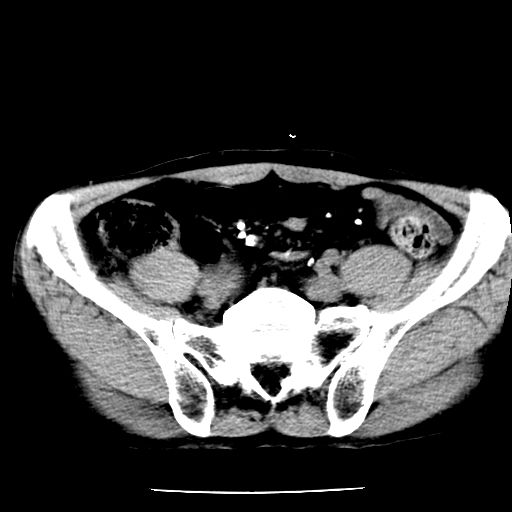

男,59岁,“结核性胸膜炎”30余年,胸部经常疼痛,多次x检查提示“肺部”炎症。腹部疼痛5日,b超提示:“肝内短管结石,余显示不清,建议进一步检查。”

两肺结核并右侧胸腔积液;脾脏、腹腔及腹膜后淋巴结结核[陈旧性];肝内胆管结石

胸部腹部都是结核(双肺。纵隔淋巴结,肝脏,脾脏,肠系膜)

两肺结核并右侧胸腔积液;脾脏、腹腔及腹膜后淋巴结结核[陈旧性];肝内胆管结石。直肠息肉?